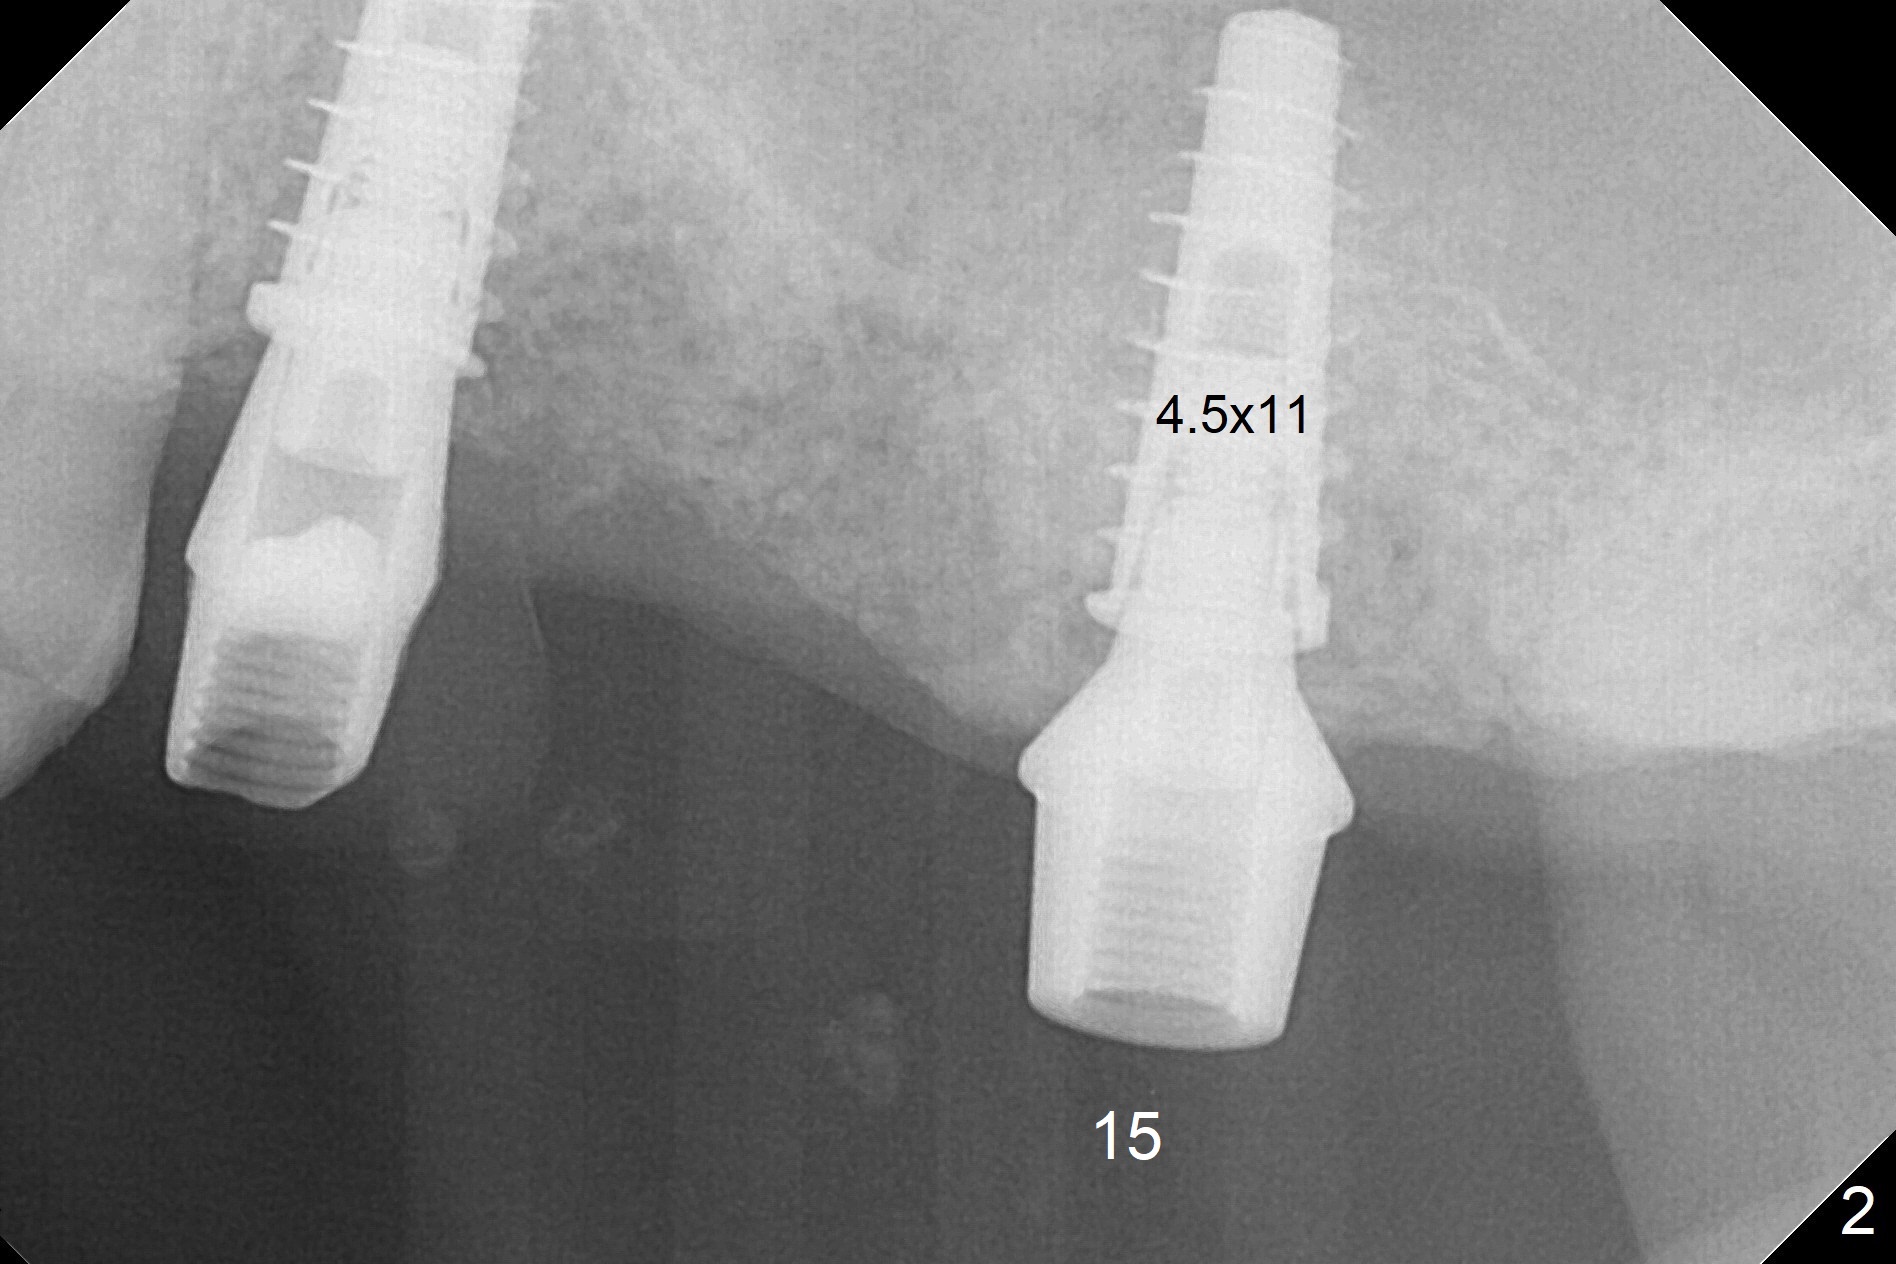

A fistula is found apical to #13 immediate implant 9 months postop (Fig.1). It is curetted without bony defect. Osteotomy at #15 is accomplished with traditional tapered osteotomes from 2 to 5 mm for 11 mm deep. Although the patient is a little uncomfortable with tapping (as compared to Magic Expanders), a 4.5x11 mm dummy implant is placed 2 mm subgingival with primary stability (Fig.2). Finally a 5x11 mm IBS implant (2 mm longer than the previous one) is placed with insertion torque > 50 Ncm; a 6x2 mm healing abutment is placed (Fig.3,4). The advantages of the flapless surgery (because of the wide ridge) include no allograft or suture. The fistula apical to #13 implant disappears 3 days postop (Fig.5), while the gingiva attaches to the healing abutment at #15 (Fig.6).